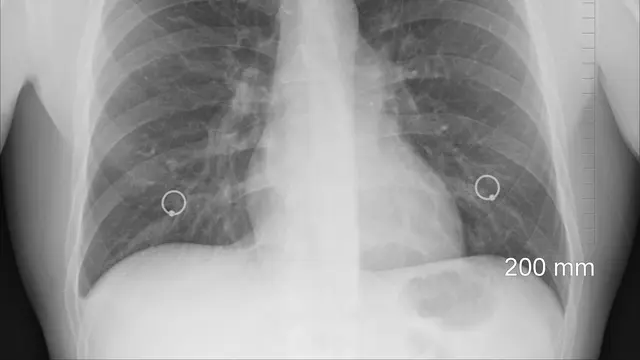

Dilansir dari Dream.co.id, pada Ilmu Kedokteran Radiologi, pemerintah Provinsi Hubei menggunakan teknik yang dikenal dengan istilah Ground-glass opacity (GGO). GGO ini merupakan Teknik CT Scan yang digunakan untuk tes virus corona.

Menggunakan metode GGO ini, membuat para dokter lebih cepat mendiagnosa suatu virus. Termasuk virus COVID-19. Agar pasien bisa lebih cepat ditangani dan disembuhkan.

Teknik Ground-glass opacity dianggap kurang akurat. Sebenarnya melakukan tes dengan tes darah, hasilnya akan lebih akurat. Tetapi para dokter di Wuhan tetap menggunakan teknik GGO ini.

Dokter memiliki alasan khusus untuk menggunakan teknik GGO ini. Karena tenaga kesehatan di rumah sakit kehabisan alat pelindung diri atau APD. Kalau tenaga medis melakukan tes darah, harus menggunakan alat pelindung yang lengkap. Karena mengambil sampel darah merupakan hal rawan terkena virus corona.

Seorang pasien yang didiagnosis suspect COVID-19, akan melakukan tes dengan CT scan. Kemudian hasil scan akan dilihat pada bagian paru-paru. Jika orang tersebut positif, maka pada bagian paru-parunya akan nampak bercak-bercak putih. Bercak ini membentuk ground-glass dan berjumlah banyak.

Jika dilihat melalui CT Scan, paru-paru pada orang normal dan sehat, memiliki ciri-ciri berwarna hitam.

Menurut Paras Lakhani, yang merupakan ahli radiologi di Universitas Thomas Jefferson, bercak-bercak putih pada paru-paru pasien belum pasti karena terinfeksi virus Covid-2019.

Bercak-bercak tersebut bisa menunjukkan banyak jenis infeksi, bakteri, virus dan tanda penyakit tidak menular. Bercak-bercak putih yang wajib diwaspadai adalah bercak yang meluas ke tepi paru-paru.